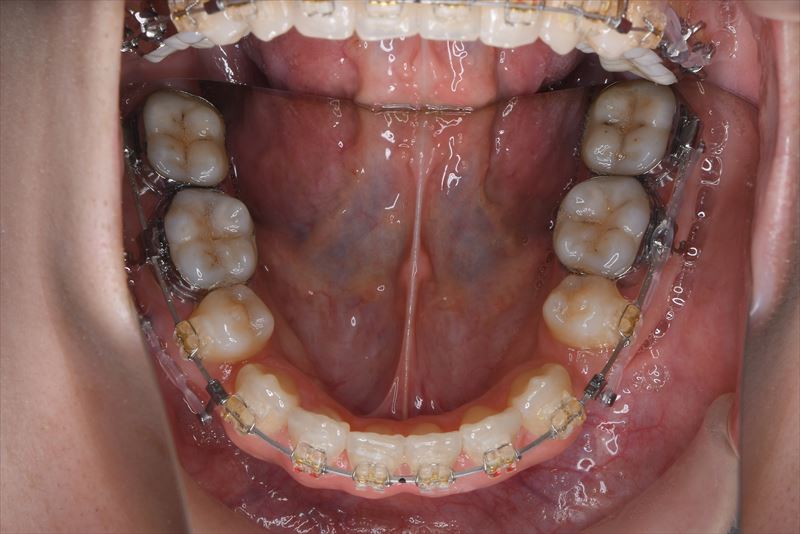

治療中

マルチブラケット装置、アンカースクリュー

上顎両側4番抜歯、下顎両側4番抜歯、下顎両側8番抜歯